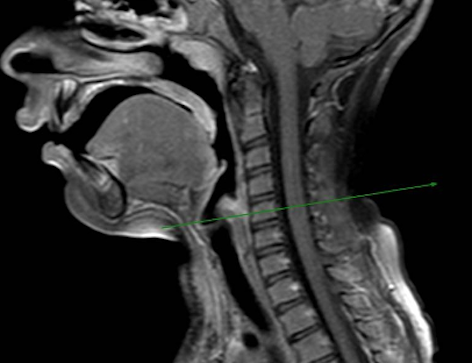

Veniva eseguita dunque risonanza magnetica del collo, con riscontro di cisti della IV tasca branchiale con tragitto fistoloso del seno piriforme complicata da flemmone dei tessuti molli del collo (Figura ). In considerazione del quadro indicativo di tiroidite suppurativa, si avviava terapia antibiotica con ceftriaxone (100 mg/kg/die) e clindamicina (30 mg/kg/die), con successivo isolamento di S. pyogenes al tampone colturale faringeo. Si procedeva successivamente all’exeresi chirurgica della neoformazione cistica del IV arco branchiale sinistro con cauterizzazione dell’orifizio della fistola. In seguito al trattamento antibiotico e chirurgico, la paziente non ha più presentato episodi infiammatori a carico del collo.